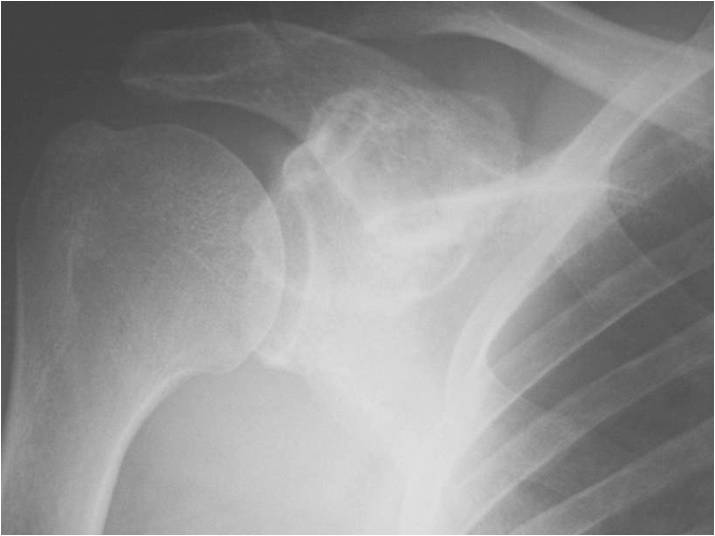

Radiographic Presentation

Radiology emulates pathology: Biphasic Tumor

- One region low grade chondrosarcoma

- Second more aggressive area with bone destruction, lysis of calcification, soft tissue mass

- Cortical permeation and a soft tissue mass in 70% of cases

Ill-defined, lytic intraosseous lesion

- Or extraosseous soft tissue mass

- Devoid of calcifications in continuity with lesions having the features of a cartilaginous tumor

Characteristically abrupt transition between chondroid tumor and dedifferentiated, lytic component

Bone may be expanded and adjacent cortex thickened

(Right Arrow)Aggressive Lytic Area (Dedifferentiated Sarcomatous Component) Cortical Destruction Soft Tissue Mass without Calcification